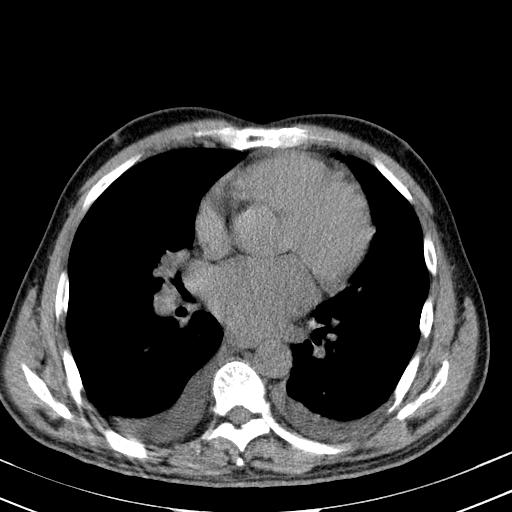

以下是引用zjzjr在2010-3-21 17:39:00的发言:[br]右下中心型肺癌并阻塞性肺炎/不张,纵膈淋巴结肿大,右侧大量胸腔积液,左侧少量胸腔积液

以下是引用zxl51642在2010-3-21 17:06:00的发言:[br]右下中心型肺癌并阻塞性肺炎/不张,纵膈淋巴结肿大,右侧大量胸腔积液,左侧少量胸腔积液,少量腹水。建议纤维支气管镜进一步检查。